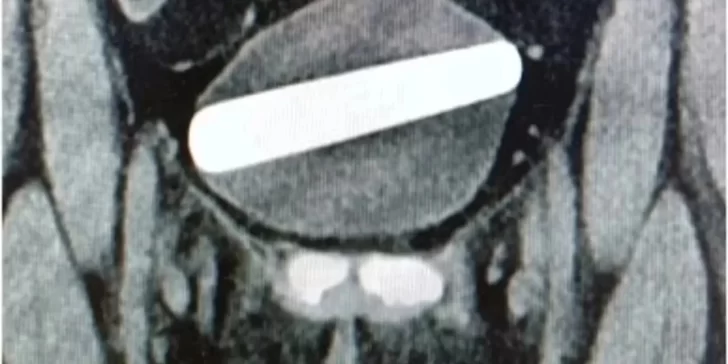

A pesar de haber estado “varias horas” intentando remover del cuerpo el objeto, que tiene casi 10 centímetros de largo y 2,5 de ancho, no pudo sacarlo. Los doctores del Shaare Zedek Medical Center de Jerusalem fueron los encargados de asistir a la mujer, cuya identidad es anónima, y afirmaron que es el “objeto más ancho” que fue removido de esta manera ya que el anterior registro fue de 2,4 centímetros.

Los médicos creen que es el “objeto más ancho” que se haya extraído de esta manera, con el récord anterior informado de 2,4 cm de ancho. Ademas, le dieron a la mujer, que había insertado el consolador para “gratificación sexual”, antibióticos a través de un goteo intravenoso.

Realizaron una cistoscopia, un procedimiento en el que se inserta un tubo largo y delgado, con una pequeña cámara en el extremo, a través de la uretra, en un intento por extraerlo. Mientras la paciente estaba bajo anestesia general, los médicos pasaron una herramienta quirúrgica llamada “grasper” a través del tubo para sacar el consolador de la vejiga a través de la uretra.